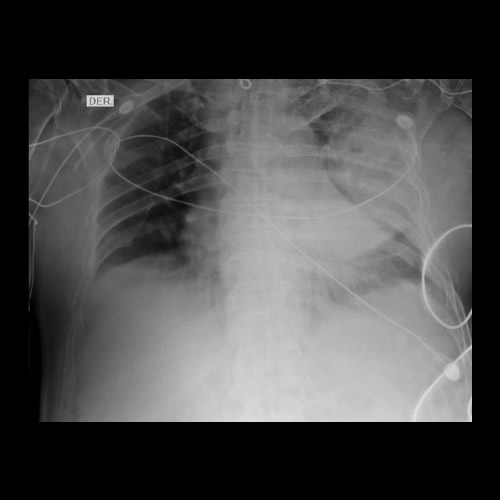

Paciente de sexo masculino de 68 años de edad, que consulta disnea CF III y tos con expectoración sanguinolenta de 7 días de evolución con registros subfebriles. Se solicita Rx de tórax.